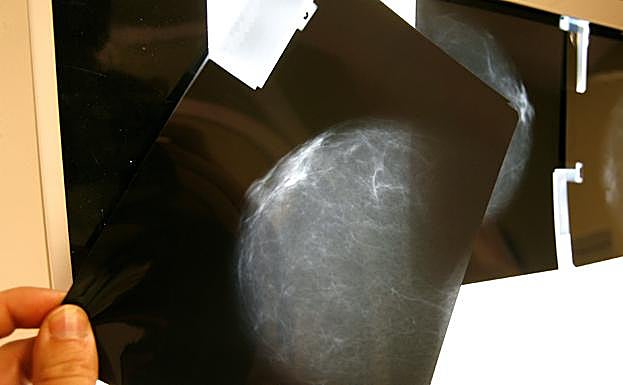

Prueba radiológica de pecho. Chema Moya (Efe)